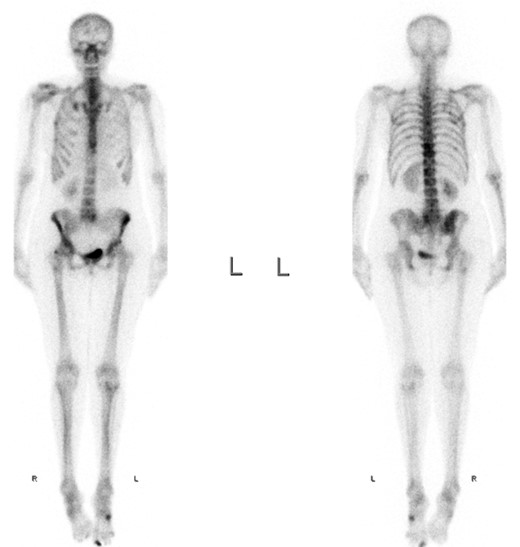

A full-body skeletal scintigraphy was done, which did not show an obvious pathology in the right TMJ (Fig. 3). Due to this, a SPECT/CT was performed for clarification. High uptake of nuclides was seen around the osteolysis of the right condyle (Fig. 4). Sclerotic changes without increased uptake were noted in the left condyle (Fig. 5).

The sclerosis of the left TMJ was suspected to be a non-active metastasis.